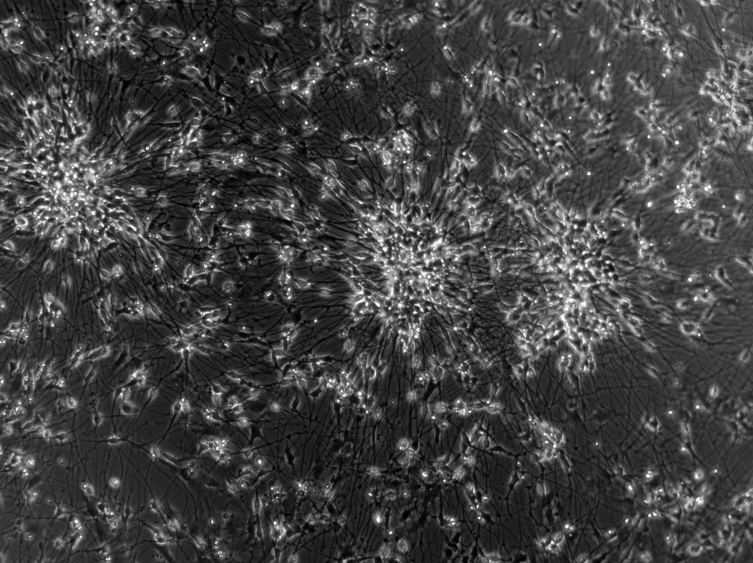

Платформа SBI меняет подход: она использует нейроны, выращенные из индуцированных плюрипотентных стволовых клеток человека (hiPSC). Эти клетки способны превращаться в любые типы клеток организма. Поместив нейроны на кремниевую платформу, ученые получили нейросети, которые могут воспринимать сигналы и отвечать на них в реальном времени, имитируя поведение мозга.

Система, получившая название DishBrain, содержит около 800 000 нейронов человека и мыши, выращенных в лаборатории. Они размещены на массиве электродов, соединенных с компьютером, который запускает упрощенную версию игры Pong — виртуального пинг-понга. Нейроны получают электрические сигналы (например, координаты мяча) и в ответ активизируются, обучаясь через процесс нейропластичности — естественную способность мозга формировать новые связи.

После 21 дня дифференциации (процесса превращения стволовых клеток в нейроны) команда протестировала три противосудорожных препарата: дифенин, перампанель и карбамазепин. Последний, в дозе 200 мкМ ≈ 47,3 мкг/мл, оказался самым эффективным — он не только уменьшил чрезмерную активность, но и улучшил поведение нейросети, сделав ее более стабильной и организованной во время игры. В клинической практике карбамазепин назначается обычно в дозах 200–1200 мг в сутки в виде таблеток.